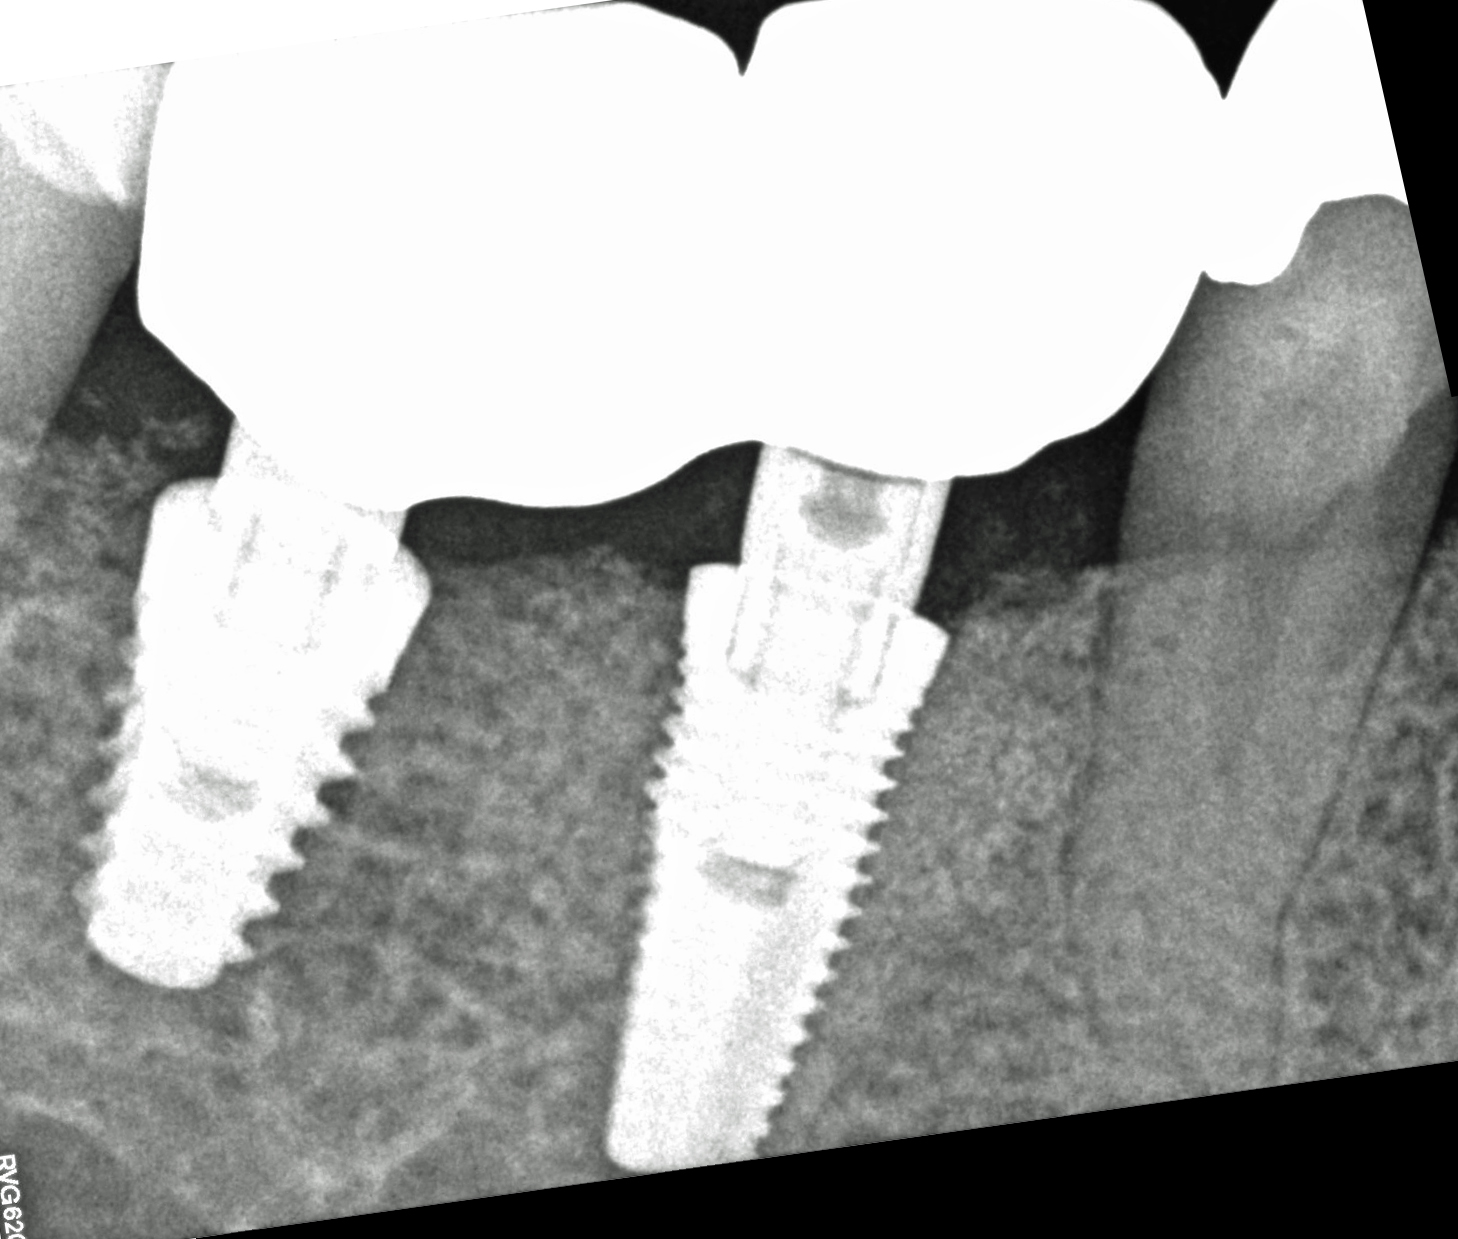

Il tunnel implantare è molto vascolarizzato. Viene inserito un impianto Neoss Tapered 4,5x11 mm, bone level, con torque di inserimento di 60 Ncm e ISQ 75 (Figure 20-22).

Dopo ulteriori quattro mesi si può procedere con l’ultima fase chirurgica di scopertura delle due fixture e di inserimento di abutment definitivi personalizzati.

Dopo l’apertura del lembo di accesso si evidenzia tessuto osseo corticalizzato anche nella zona vestibolare e crestale di 4.5. La visione occlusale consente di apprezzare la ricrescita ossea coronale alla vite tappo della fixture in 4.5 e del tessuto osseo vestibolare rispetto al bone housing. La misurazione ISQ di 4.5 restituisce l’alto valore di 86 (Figure 23-24).

Vengono cementate due corone in zirconio stratificato (Figura 29). Il controllo clinico e radiografico dopo 18 mesi mostra la buona risposta dei tessuti gengivali e la stabilità ossea perimplantare (Figure 30-31).